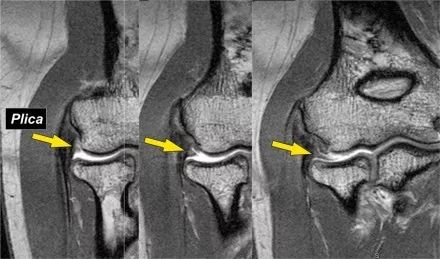

3.滑膜皱襞(plica)有时可以看到关节外侧的这种结构并且是一个皱褶。它可以是突出的,几乎看起来像半月板。这是一种正常的结构,但有时它会变厚或不规则,可能是症状的原因。